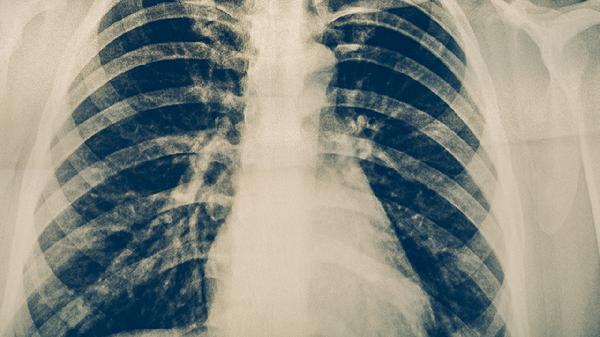

4、改善肺功能

长期服用可提升FEV1等肺通气指标,减少慢性阻塞性肺疾病患者的急性加重次数。对吸烟导致的肺肾两虚型咳喘效果显著,但需配合戒烟才能达到理想疗效。